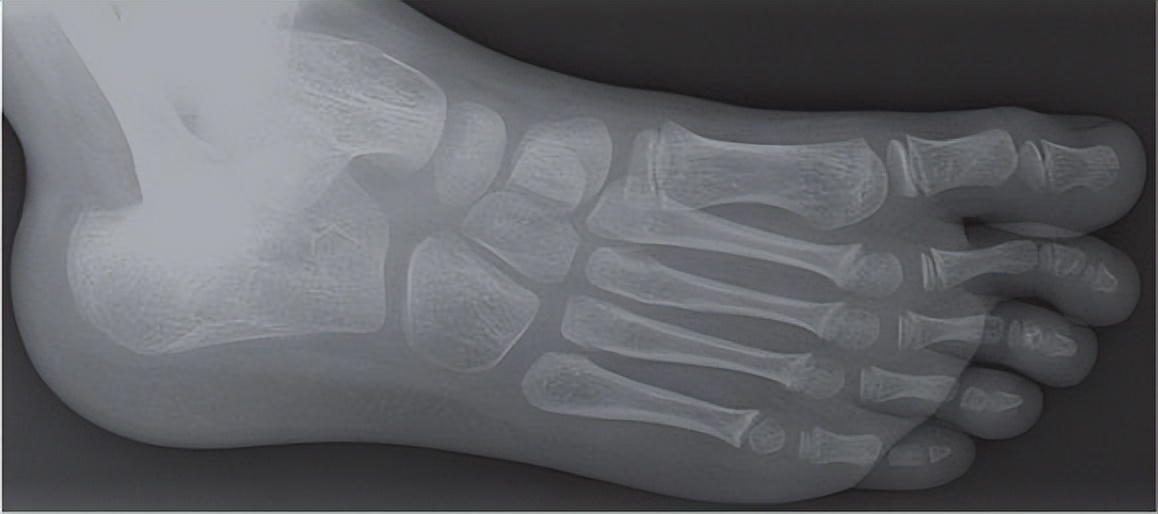

这是一个拇外翻家长给我发过来孩子脚的情况,他们家孩子12岁,非常典型的拇外翻,她就问我孩子现在12岁,这种情况可不可以做拇外翻手术。如果说你的孩子也有踇外翻,现在该做哪些事情我们权且不讲,有这么严重的,十一二岁有这么严重的还是非常少见。我在临床十多年,见到孩子,十一二岁孩子如此严重的不太多,这是个例。